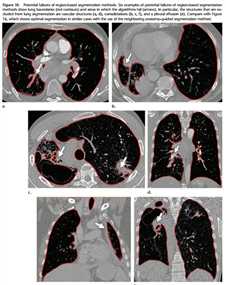

基于区域的肺部分割经常存在着假阴性,因此需要进一步的后处理。如下图。应用基于区域的分割而产生的失败案例。

对于细小病变或正常的肺部图像,只要选择合适的阈值就能对图像进行分割。然而,对于一些病变区域,虽然病变区域和肺部有相同的阈值,但是阈值区间通常将病变区域从肺部图像中剔除出去。Figure6 show了胸腔积液及实变的例子,可能需要各种形态学操作或人工假阳性删除过程以纠正生成的分割